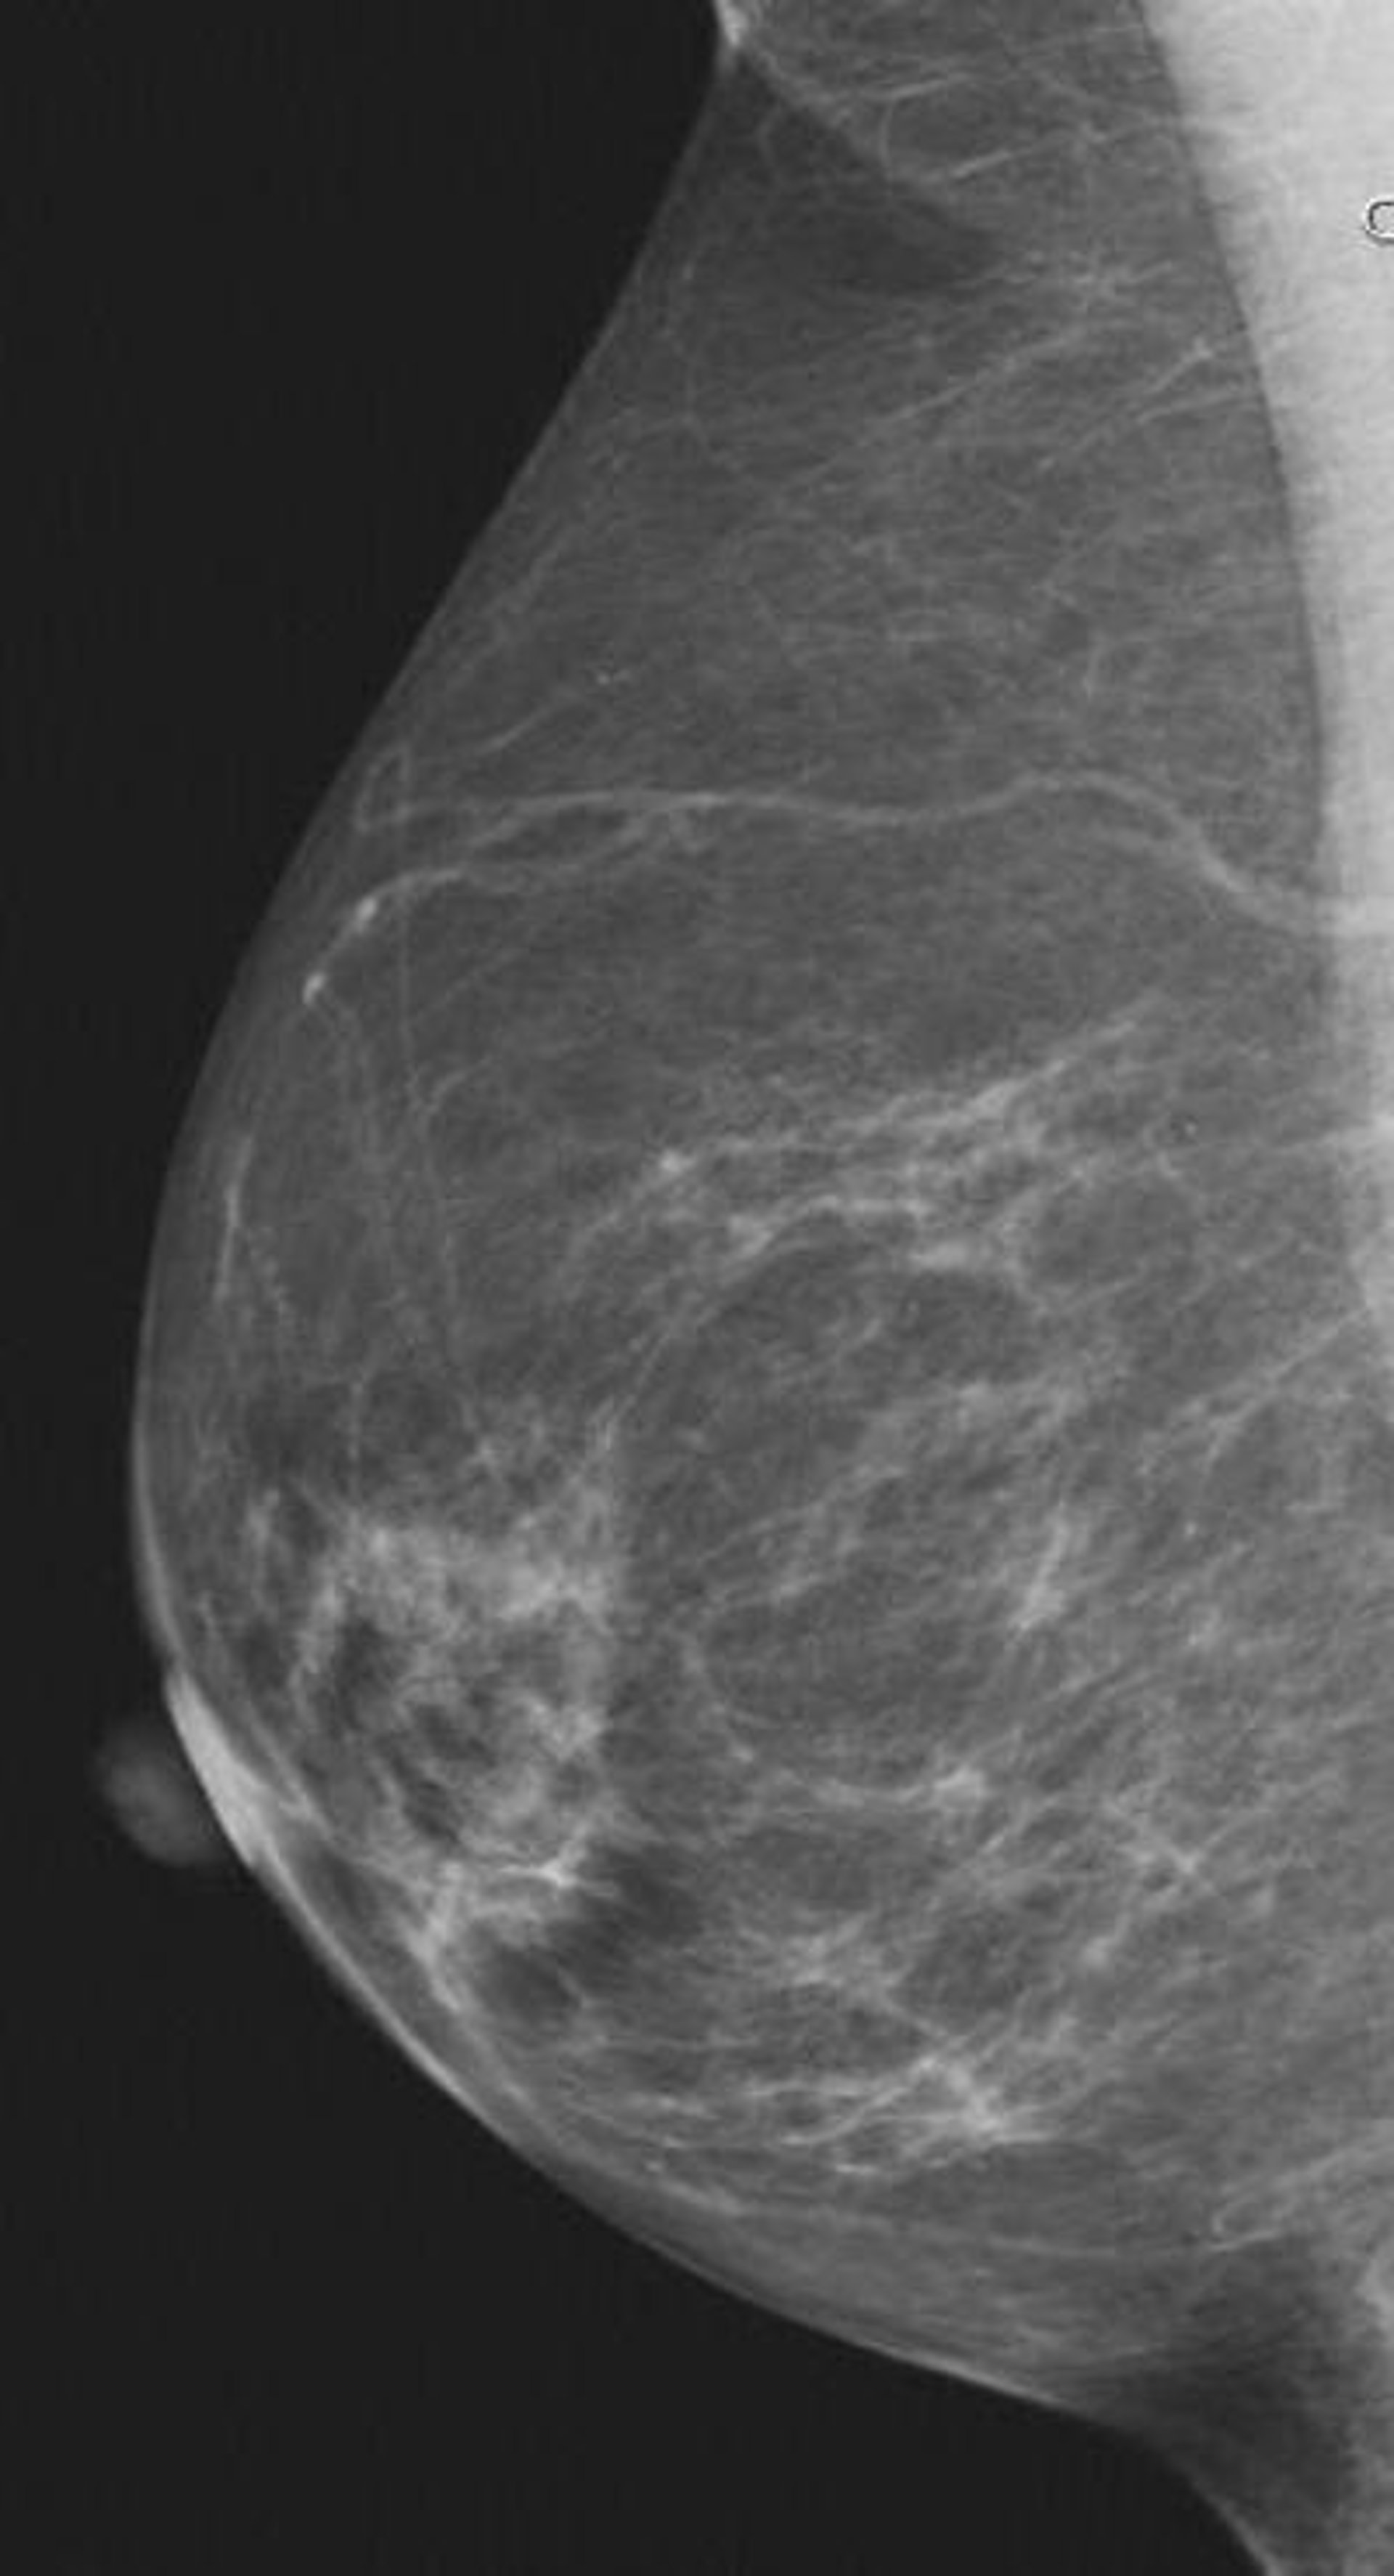

Mama, pecho

RADIOLOGICAL SOCIETY OF NORTH AMERICA